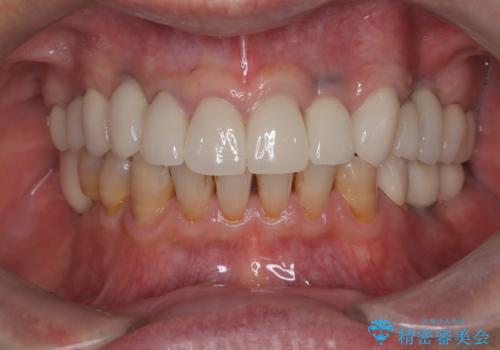

- 「被せ物が揺れている」を主訴に来院された患者様です。診査診断を行い被せ物が外れているのではなく、コアという土台ごと外れていたので、土台ごとやり変えた後オールセラミッククラウンで治療を行いました。

ファイバーコアという土台を建てるときに唾液が入ると接着に良くないのでラバーダムシートを使用しています。加えてマイクロスコープを使用しながら行う事で外れにくい土台を作ることが出来ます。その後、形成を行いシリコンで型取りしたのち、オールセラミッククラウンで修復しました。